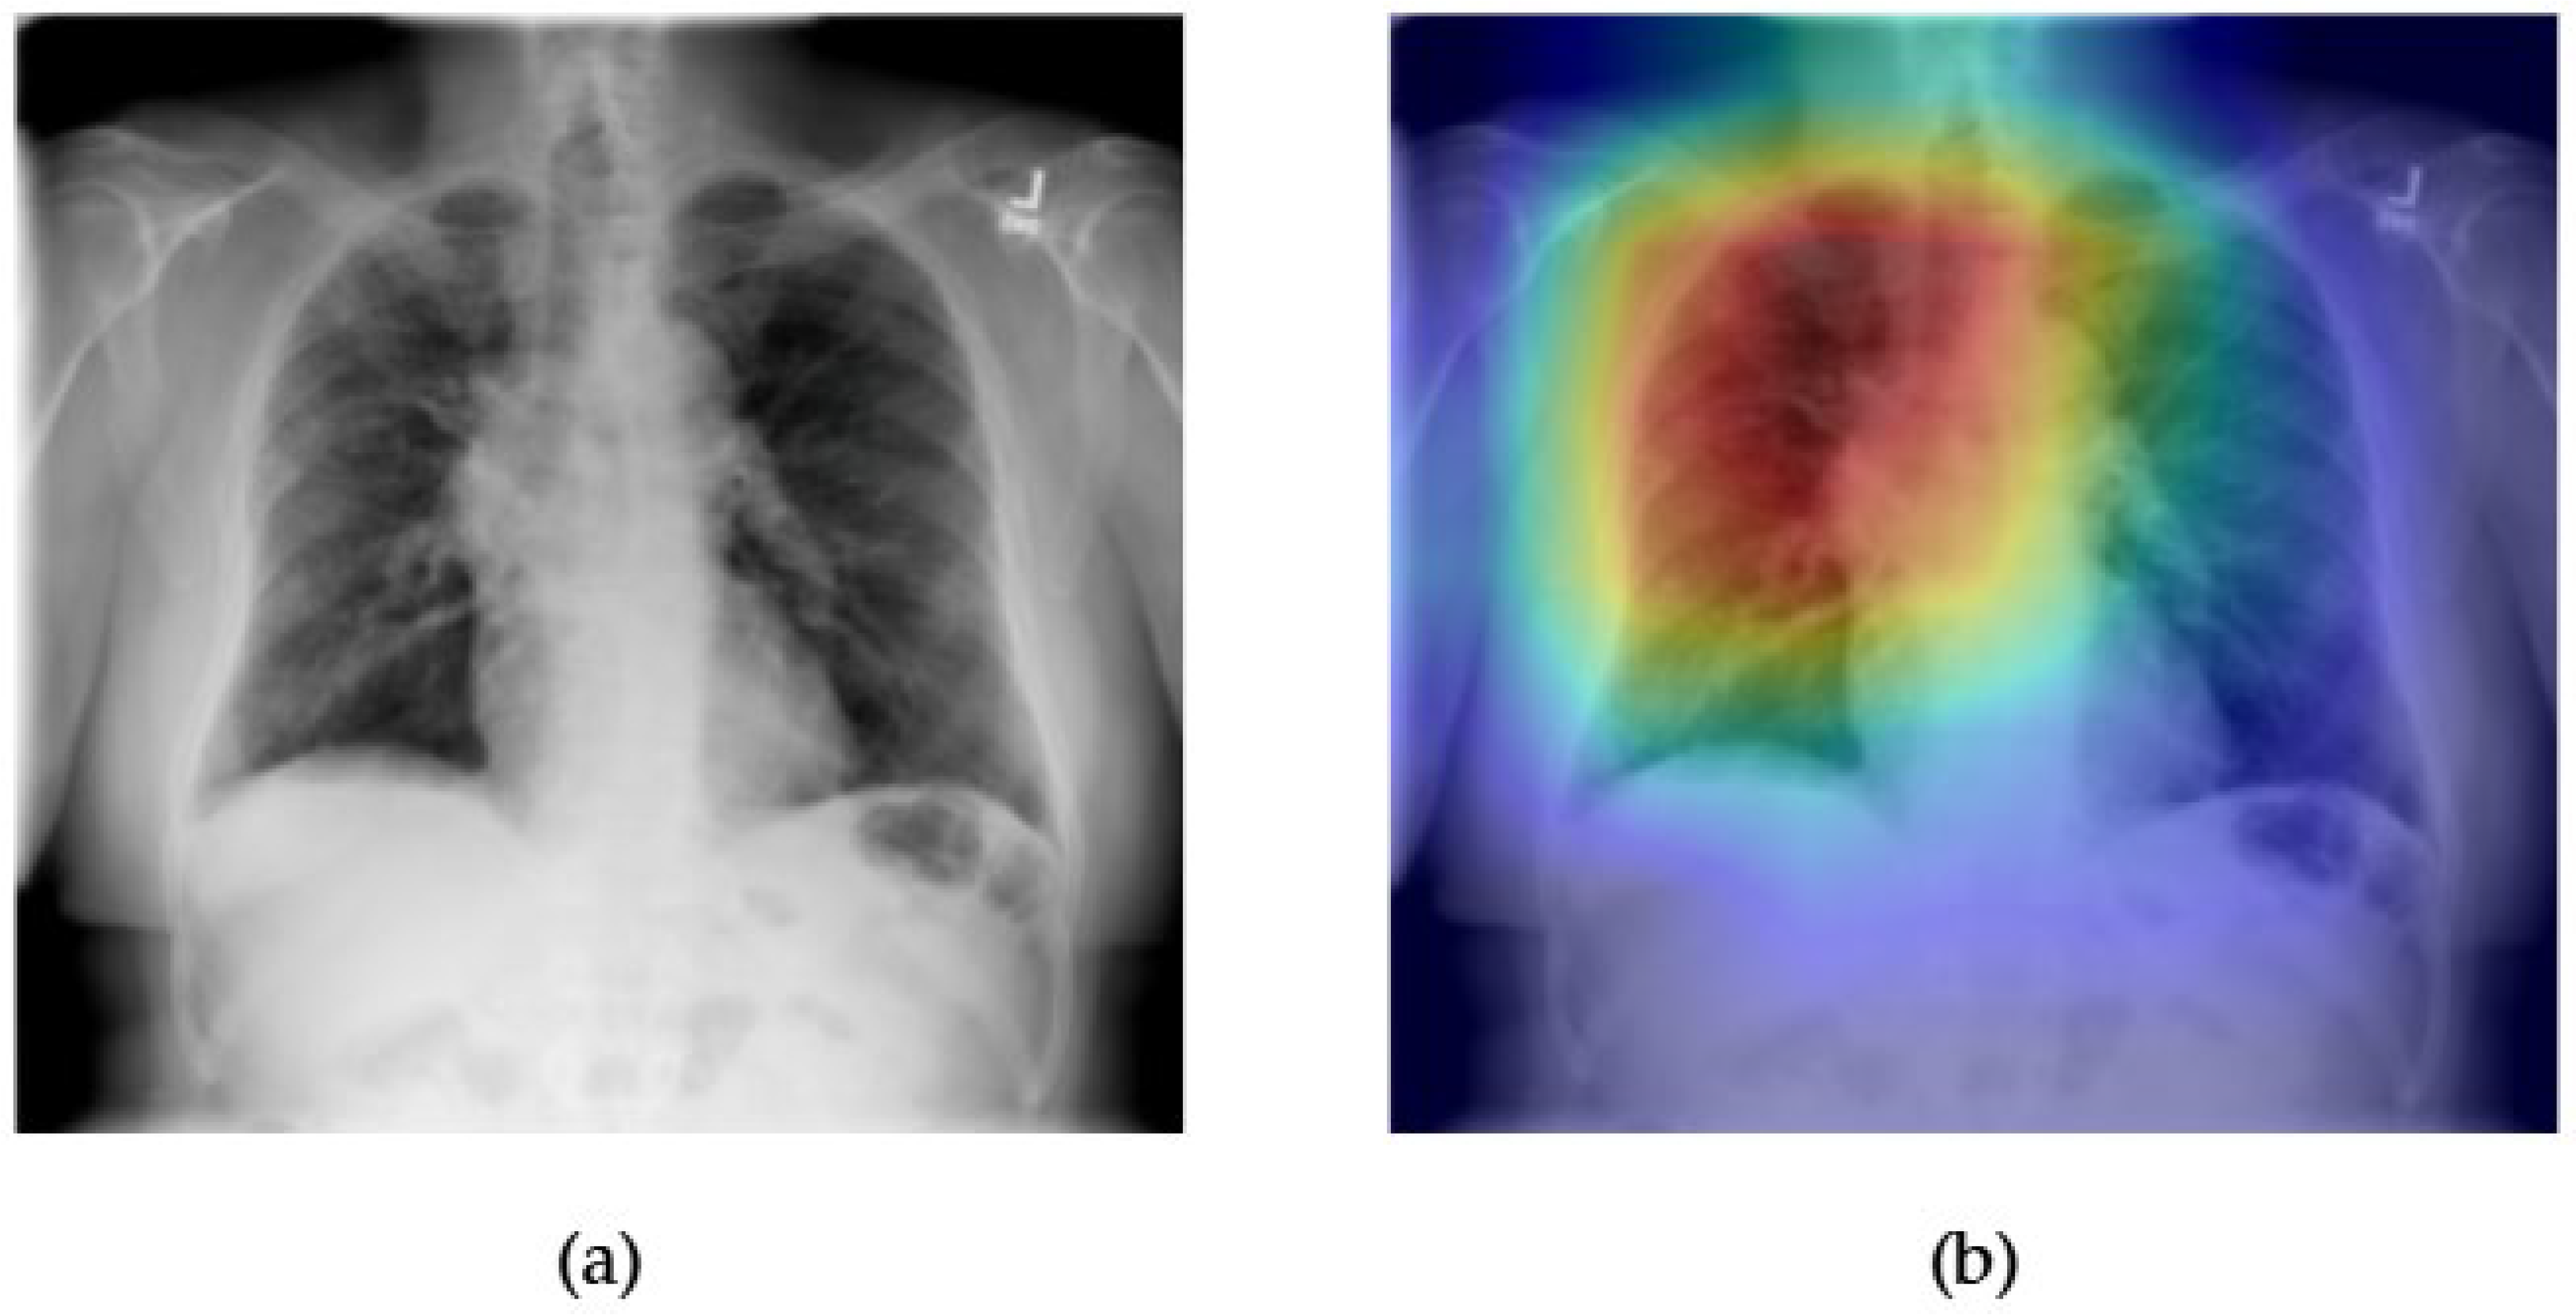

- Although our Grad-CAM-based explainability provides useful localization cues, it is inherently limited by its post hoc nature and reliance on gradient flow from the final convolutional layers. Future research could incorporate advanced interpretability techniques such as Layer-wise Relevance Propagation (LRP), Integrated Gradients, or attention rollouts in Transformers, which may offer a more complete understanding of model reasoning.